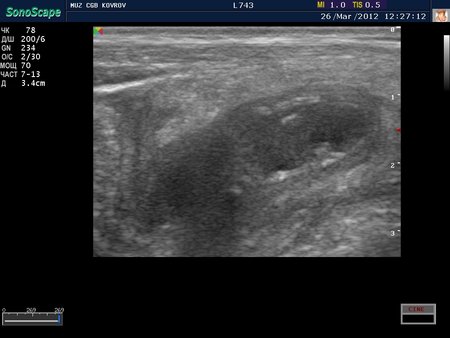

Как вы думаете, что это??? ;)

жидкостная тубулярная структура с конкрементами?

1. Воспаленный аппендикс, копролитами- фекалитами... :)

но скорее первое, чем второе..

Serg, вы правы. п1-совершенно верно!!! :D

О.аппендицит с картиной о.холецистита )